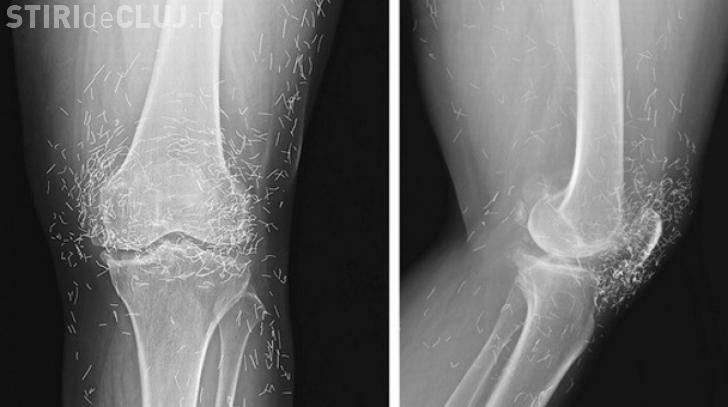

Atunci când au examinat cu ajutorul razelor X genunchii unei femei care acuza dureri cumplie în zona încheieturilor cu pricina, medicii au descoperit o veritabilă mină de aur.

Sute de vârfuri de ace, toate de aur, fuseseră lăsate deliberat în țesuturile pacientei în urma unor obscure ședințe de acupunctură la care aceasta fusese supusă.

Pacienta în vârstă de 65 de ani fusese diagnostică inițial cu osteoartrită, o afecțiune ce duce la degradarea cartilagiilor și a oaselor din zona încheieturilor, provocând rigiditatea acestora și, implicit, dureri acute. Însă cum medicamentele antiinflamatorii sau cele care ar fi trebuit să reducă durerile femii nu au avut niciun efect, aceasta a apelat la tradiționala acupunctură, se arată în studiul medicilor care au analizat neobișnuitul caz, studiu prezentat în New England Journal of Medicine, scrie stiintasitehnica.com

Trebuie spus, pentru cei care nu știu deja, că acupunctura reprezintă o practică medicală alternativă ce implică introducerea unor ace în piele și țesut uman, totul cu scopul de a stimula anumite puncte prin care, susțin practicanții acesteia, pot reduce durerile sau chiar vindeca o serie de boli. În cazul prezentat mai sus, vârfurile acelor de aur au fost rupte deliberat și lăsate în genunchii femeii cu scopul unei stimulări continue. Nu este prea greu de imaginat ceea ce a urmat, credulitatea pacientei ducând-o pe aceasta aproape de un dezastru. Cu atât mai mult cu cât oricine ar trebui să știe că un corp străin introdus într-un organism va duce, mai devreme sau mai târziu, la inflamații și infecții.

”Organismul uman are tendința naturală de a scăpa de corpurile străine. Totul începe cu mecanismele simple de apărare, etapă în care apar inflamațiile. Apoi, organismul nostru formează țesuturi fibroase în jurul corpurilor pe care nu le poate distruge sau elimina. Atunci când avem un caz ca acesta există și alte probleme majore. Spre exemplu, pacienta nu poate fi supusă unei examinări RMN, și asta pentru că în timpul examinării acele se pot mișca în corp, atingând arterele sau alte vase importante de sânge”, afirmă dr.Ali Guermazi, radiolog în cadrul Universității Boston.